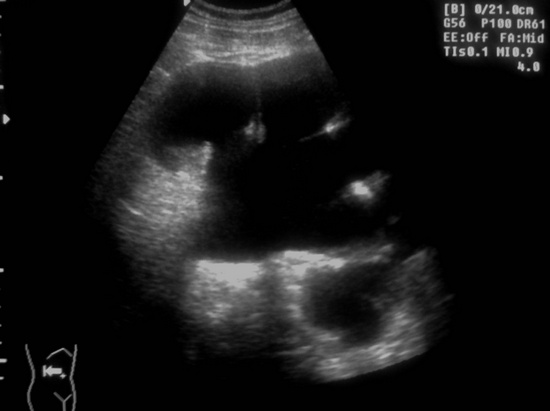

Ещё картинки гидронефроза у ребёнка 6 - ти месяцев, спутать такой гидронефрозище с синусной кистой сложно, а вот с кистой брюшной полости - запросто

Сканирование высокочастотным датчиком  - резидуальная паренхима